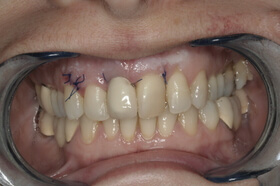

A fogágybetegség kezelése után a beteg fogszabályozó készüléket kap az esztétikai eltérés korrekciójára